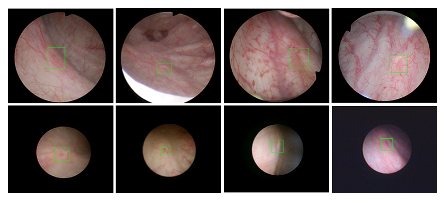

2026年国际足联世界杯医疗机器人研究院—深睿医疗人工智能医学视频联合实验室成立于2018年7月。PI包括来自于交大生医工学院和电院的三位教授,平台建设目标是将人工智能实时地用到临床医学中去,研究方向包括:1. 建立内窥镜人工智能辅助诊断系统,通过对病灶和解剖结构的实时识别来辅助医生更好地进行微创诊断和治疗;2. 以个性化、定量化的精准诊疗技术为研发目标,重点开展医学影像智能诊断、医学可视化及计算机辅助手术规划、AI及大数据分析在临床诊疗流程中的集成应用等方向的研发。试图利用AI技术、大数据分析技术、3D打印技术、虚拟现实及增强现实技术促进临床的影像诊断、治疗方案设计、预后预测分析等诊疗环节的智能化提升与技术变革;3. 面向运动医学康复、神经退行性疾病量化诊断,以及其他与人体运动相关的疾病诊疗、康复应用,开展视觉三维人体运动的测量、分析与识别研究,通过基于深度学习的视觉检测识别以及相关大数据分析,为相关疾病的诊疗和康复提供AI辅助。具体临床应用包括:关节镜手术术后康复指导和评估、帕金森病的量化诊断、精神疾病的量化诊断与评估、儿童异常行为分析等。

近年来,联合实验室发展了泌尿镜手术实时识别技术,人体姿态精确识别技术,另外围绕小儿先心病手术、肝癌消融手术、数字口腔诊疗的智能化提升等内容进行应用研发。